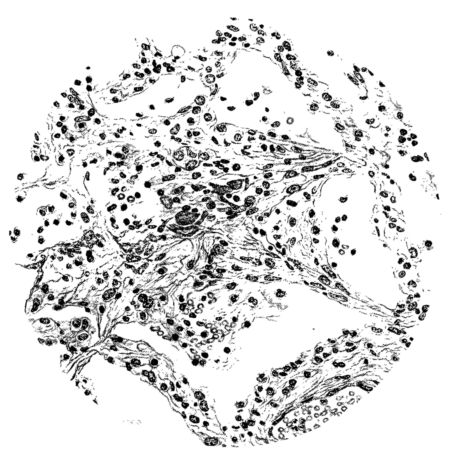

FIG. III. AUTOPSY NO. 90. DRAWING FROM A LESION OF THE TRACHEA (SOMEWHAT OLDER THAN THAT ILLUSTRATED IN FIGURE II). THE MUCOSA IS ENTIRELY LACKING. CONGESTION AND EDEMA ARE THE STRIKING FEATURES IN THE SUBMUCOSA. THE NECROTIZING PROCESS HAS EXTENDED INTO THE MUCUS GLANDS. THIS IS SHOWN IN THE LOWER PICTURE.

The changes are less marked, perhaps, in the trachea than in its finer ramifications. The mucosa is constantly more or less destroyed and large areas, usually focal, are entirely devoid of their epithelial covering. This is replaced by a sparse exudate, composed largely of red blood cells, mucus, a small amount of fibrin, and nuclear fragments (Fig. II). It may dip into the submucosa for a short distance, but usually these indentures are associated with the ducts of the mucous glands into which the inflammatory reaction extends. A more striking feature than the exudate, however, is the edema and the congestion of the submucosa. The loose areolar tissue of the submucosa is spread widely apart, and throughout it distended blood vessels are very conspicuous. Occasionally such a vessel is broken and actual hemorrhage appears in the submucosa. Occasionally, too, the inflammation extends down the duct to the mucous gland itself, and here, also, aplastic inflammatory reaction is evident, inasmuch as the acini now stain intensely red with the cells undifferentiated from each other and specked here and there by broken remains of the dead nuclei (Fig. III). After the disease has continued for a short period, even at the end of five or six days, some regeneration of the epithelial lining may be seen (3) (Fig. IV). But despite this, the acute picture persists, and there goes on, side by side, an attempted repair characterized by epithelial regeneration and the same evidence of acute change. Since the lesion is essentially a superficial one, scars or contractures of any extent are not encountered in the trachea, even in examples of the disease that have ended fatally only after many weeks.[4]